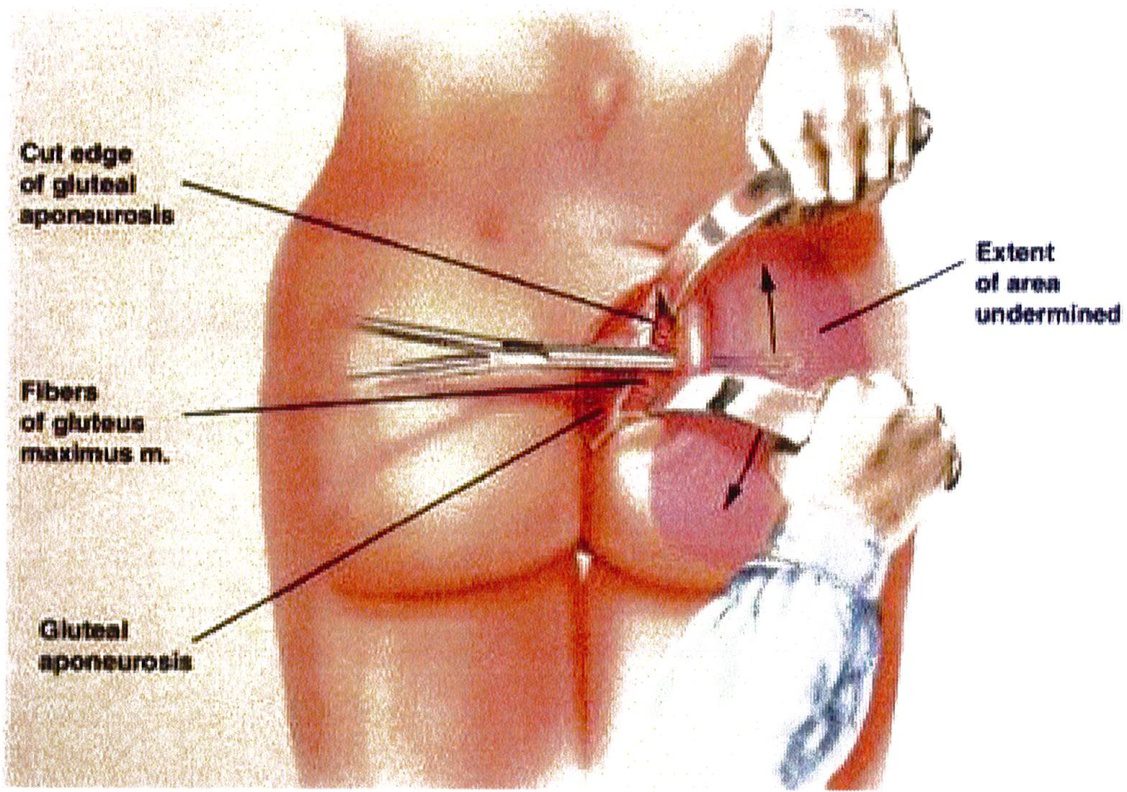

khu vực dưới cân, từ đó có thế bóc tách được lớp cân mạc nguyên vẹn (Hình 9). Các vách ngăn này chạy cùng chiều với các bó cơ mông mà chúng che phủ tương ứng, nên khi bóc tách trông chúng như đang tỏả ra như hình rẻ quạt.

Extent of area undermined

Hình. 12. Bóc tách mặt phẳng dưới cơ trước khi đặt sizer để ước tính vị trí, kích thước khối implant khi đặt vào (From de la Pena JA, Rubio OV, Cano JP, et al. Sub- fascial Nâng mông. Clin Plast Surg 2006;33:412; đã xin phép trước khi đăng tải.)